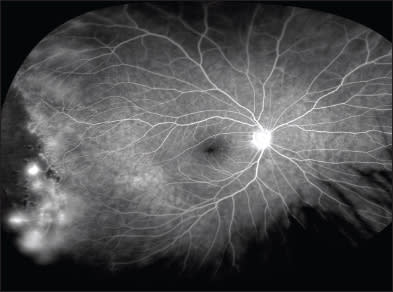

Widefield angiography also allows for better evaluation than small-angle angiograms of peripheral pathology, such as retinal nonperfusion and perivascular leakage, which may have important implications for posterior-pole pathology (Figure 2).

It was recently demonstrated that peripheral retinal ischemia was significantly correlated with diabetic macular edema, suggesting that treatment of peripheral disease may one day be considered a treatment option for DME.20 A different study showed that perivascular leakage, as demonstrated by widefield imaging, was associated with neovascularization and possibly with macular edema.21

Given that neither the degree of retinal nonperfusion nor perivascular leakage was used as a criterion in ETDRS or the Diabetic Retinopathy Study, these markers of disease pathology may play an important role in our future management of diabetic retinopathy, and future studies may help elucidate their importance.

Figure 2. A widefield angiogram of proliferative diabetic retinopathy showing extensive peripheral capillary dropout and peripheral perivascular leakage (imaged with the Optos 200 Tx).